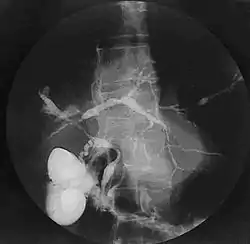

![]() صورة الأقنية الصفراوية لالتهاب الأقنية الصفراوية المصلب الابتدائي صورة الأقنية الصفراوية لالتهاب الأقنية الصفراوية المصلب الابتدائي | |

يتم التشخيص عن طريق التصوير الأشعاعي للطرق الصفراوية في ما يسمى ب(بالإنجليزية: endoscopic retrograde cholangiopancreatography). ويتم هذا التصوير عن طريق حقن صبغة ملونة في الطرق الصفراوية من خلال منظار معوي. وتعمل الصبغة على تلوين الصور الأشعاعية ليتمكن الجراح من رؤية قياس وأبعاد هذه الطرق. ومن الممكن الأستعاضة عن هذه الطريق بالرنين المغناطيسي (بالإنجليزية: magnetic resonance cholangiopancreatography).